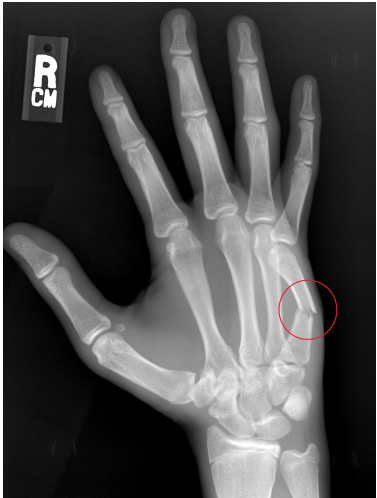

Identify the most common MOI for fracture of 5th metacarpal and describe why this occurs

Punching with closed fist places big axial load on metacarpal head causing transverse (most commonly) fracture of metacarpal shaft/head